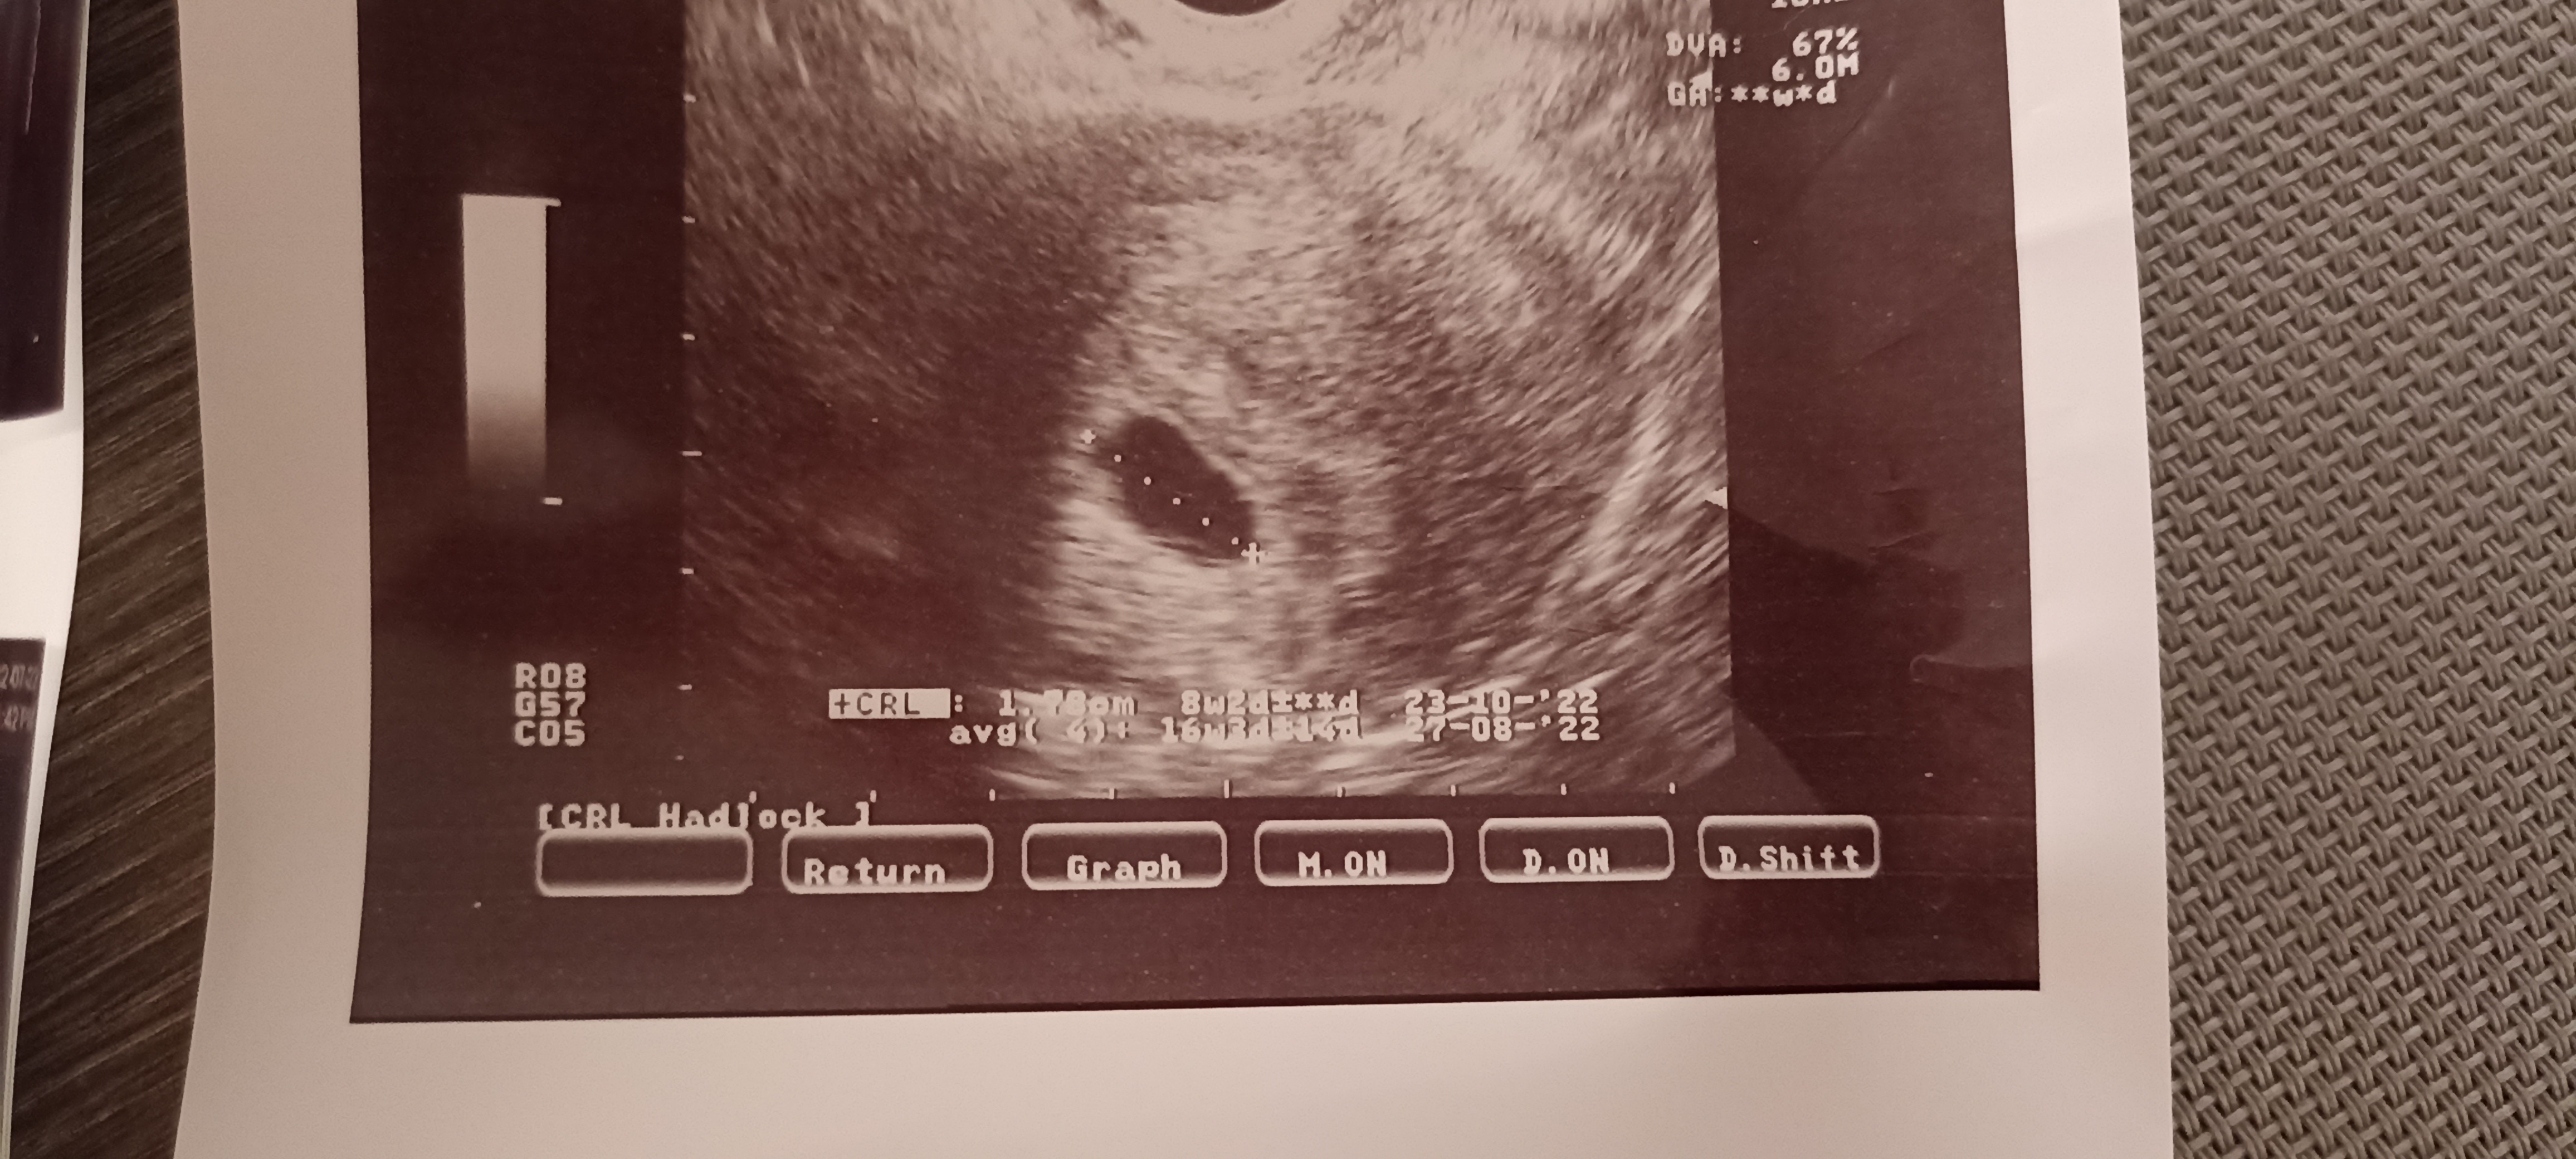

Witam , jestem w Uk - stad moje mega obawy chyba. Ostatnia miese miałam 7/08. Test pozytywny 4/09 w dzień spodziewanej miesiączki. Według obliczeń poszliśmy na usg w 7+6 tyg (25.09). Babeczka robiąc usg wykryła puste jajo płodowe z nawiązką krwi obok jaja. Powiedziała ze może to być puste, małe jajo płodowe albo 5 tydz ciąży dopiero, z tym ze nie jest widoczne ciałko żółte. Dwa dni po badaniu plamienia różowe , potem brązowe, bol brzucha pojechaliśmy do szpitala - dalej pusto ale mówią , plamienia to normalka, bol brzucha to normalka No i czekać za dwa tyg scan. Według moich obliczeń mega niemożliwością jest żebyśmy byli w piątym tyg dopiero bo sex uprawialiśmy 19/08 (20/08 wypadała ovulacja) prosze bez ocianiania ale potem nie mieliśmy sexu do 3/9 dzień nastepny robiłam test który wyszedł pozytywnie. Ja rozumiem ze może się wszystko poprzesuwać ale cykle mam co 28 dni, regularne. No i te plamienia teraz z bolącymi plecami i podbrzuszem. Zamartwiam się totalnie. Mial ktoś taka sytuacje ? Kiedy wszystko wydaje się kalendarzykowo a jednak te 2 wielkie tyg wszystko się przesunęło ??

A to z mojego skanu (25/09)

Mam możliwość pójścia prywatnie w piątek 30/09, na scan znowu ale nie wiem czy jestem w stanie usłyszeć po raz 3 puste jajo płodowe.